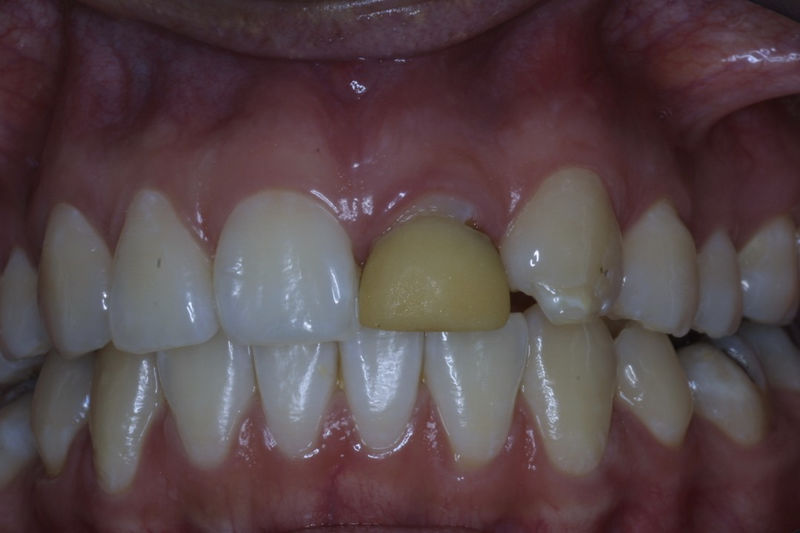

Amplia gama de tratamientos para mejorar la apariencia de la sonrisa, corrigiendo el color, la forma, el tamaño, la alineación y la posición de los dientes. Los procedimientos más comunes y solicitados incluyen el blanqueamiento dental, las carillas y coronas, así como las resinas.

Son restauraciones que cubren toda la cara frontal del diente, generalmente empleadas en el sector anterior y cuya finalidad es primariamente estética.

Restauraciones fabricadas en el laboratorio con materiales estéticos, los cuales cubren de manera total dientes anteriores y posteriores. Se utilizan primariamente para restaurar dientes con caries, fracturas y/o defectos amplios, así como soportes de puentes. Para poder enviar el caso al laboratorio se toman impresiones utilizando materiales de impresión o técnicas modernas digitales.